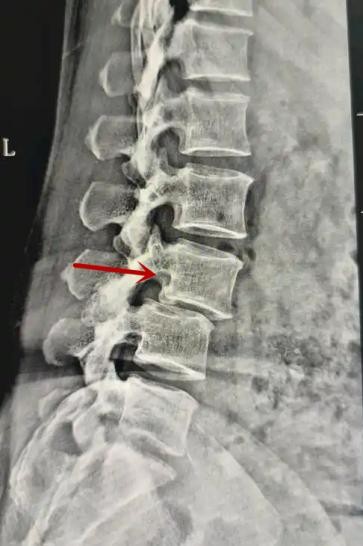

箭頭提示腰1椎骨折

箭頭提示腰3椎體滑脫

紅色箭頭提示新鮮骨折,黃色箭頭提示陳舊性骨折